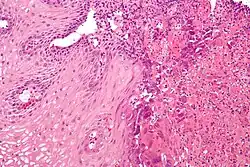

Esophagitis can be diagnosed by upper endoscopy, biopsy, upper GI series (or barium swallow), and laboratory tests.[4]

An upper endoscopy is a procedure to look at the esophagus by using an endoscope. While looking at the esophagus, the doctor is able to take a small biopsy. The biopsy can be used to confirm inflammation of the esophagus.

Laboratory tests can be done on biopsies removed from the esophagus and can help determine the cause of the esophagitis. Laboratory tests can help diagnose a fungal, viral, or bacterial infection. Scanning for white blood cells can help diagnose eosinophil esophagitis.